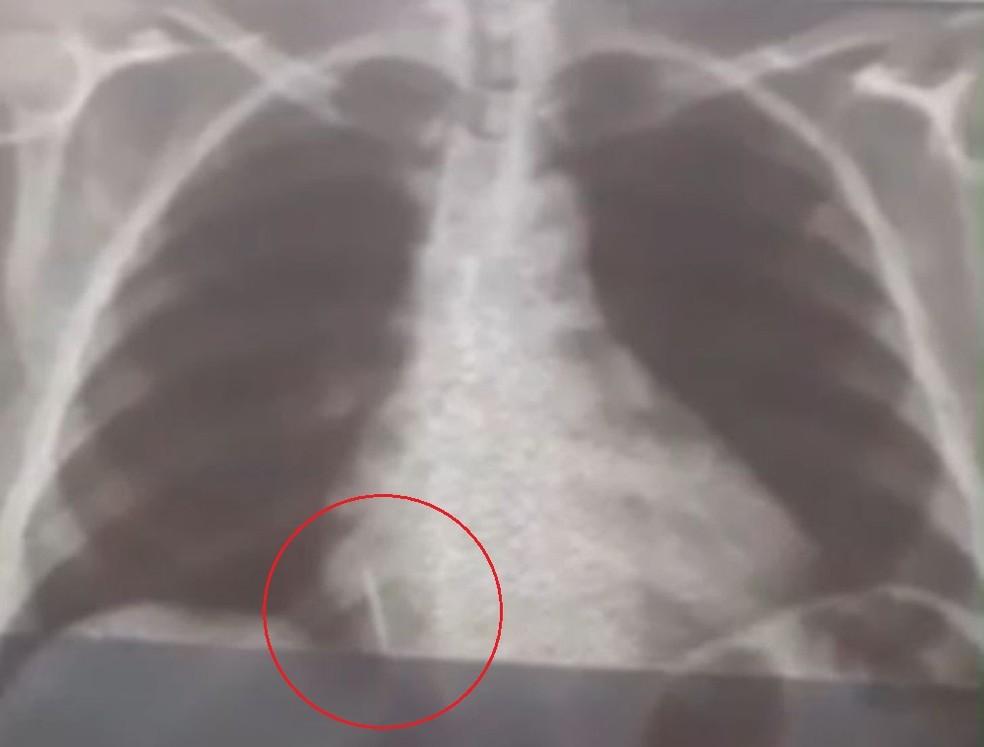

Legenda: Cirurgia para retirada do objeto ainda não foi feita por equipamento necessário ter quebrado

Uma paciente de 55 anos passou por complicações após uma consulta ao dentista no Rio Grande do Norte. Ela engoliu uma broca durante a extração de um dente, no último dia 26 de julho. Ela permanece com o material alojado no pulmão desde então, já tendo perdido cerca de 10 kg desde o ocorrido. As informações são do portal G1.